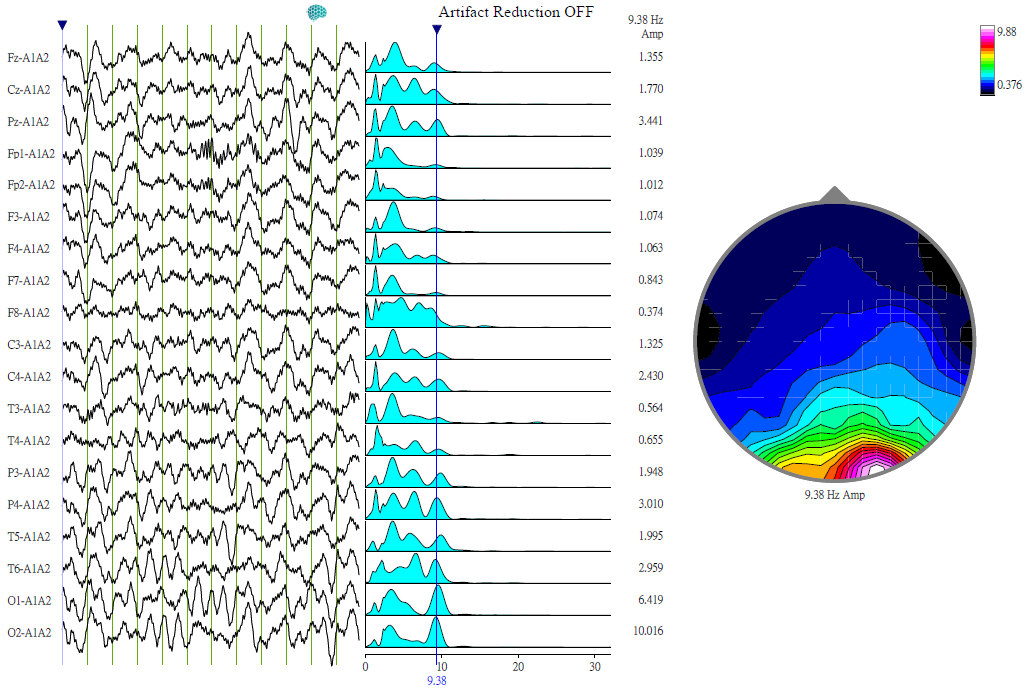

通过与普通人的EEG脑波检测结果作比对(关于EEG脑波检测,请移步人人生而不同,请多一分理解),发现自闭症人士的脑波存在以下特点:

自闭症特征性脑电图

自闭症人士大致上在前额叶与顶叶缺乏α波,α波主要存在于枕叶。α波与认知、信号的处理相关。这种脑波的分布特点,决定了其视觉信息进入脑部后,经由枕叶处理并往前传送至前额叶时,前额叶却难以处理。为了避免前额叶处理信息造成过度耗能,所以他们会避免与人眼神交流。因为人类面部表情传递较多信息,如不能处理,个体的自我保护机制就会启动——尽量不要有眼神交流,以避免信息超载。

另外,前额叶是社会化功能的重要区域,自闭症人士前额叶缺少α波,所以表现出社交困难。视觉信息投射在大脑的后枕叶,所以部分后枕叶α波分布较多的自闭症人士会表现出超于常人的视觉信息处理能力。

通过EEG脑波检测这种客观的检测和评估方式,让我们能更好地认识与理解自闭症的各种特点。更重要的是,它是制定个性化治疗方案和评估治疗效果的客观依据。而治疗的手段,则是通过BRC项目个人化、动态化的经颅磁刺激治疗。